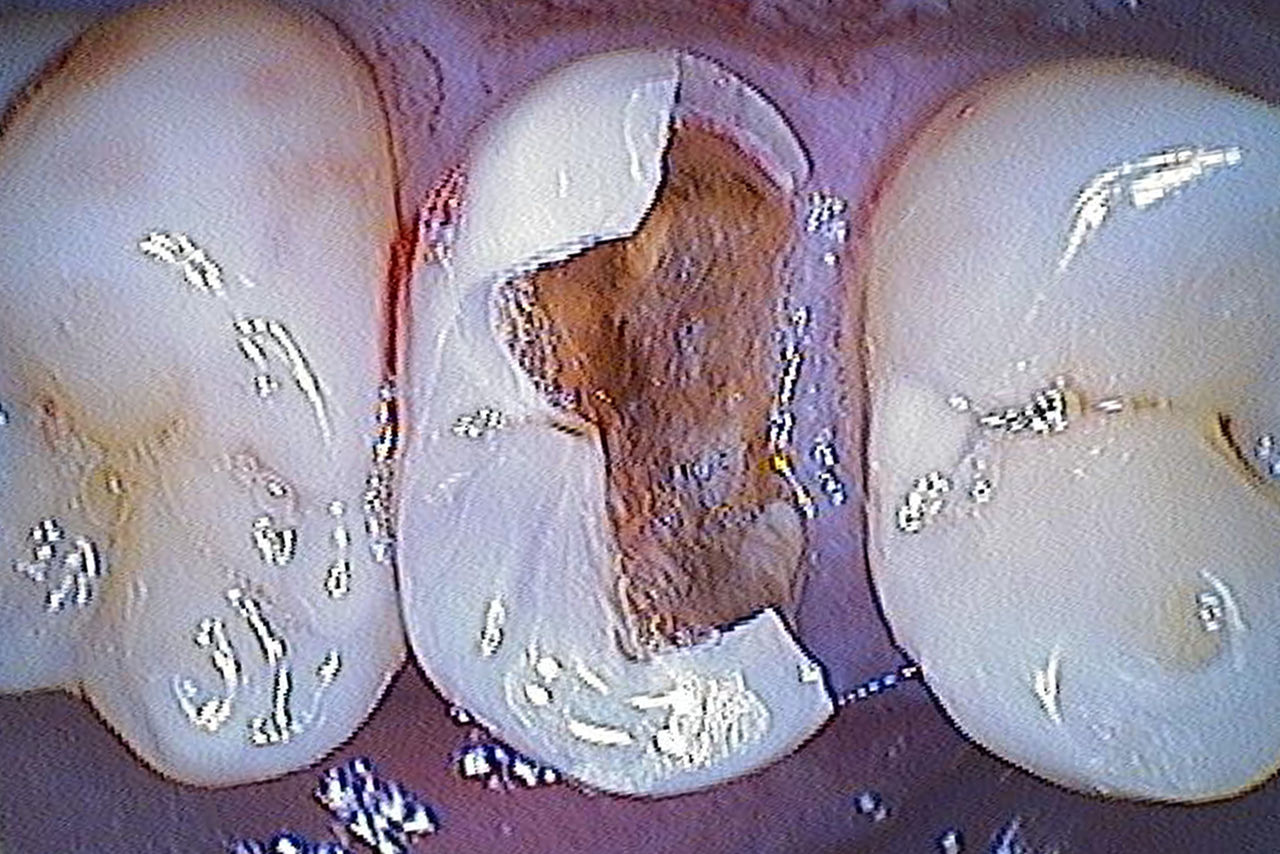

Composite filling, tooth 16, before CEREC treatment

Before

Large insufficiency of the composite filling on tooth 16 with distal marginal ridge cracks, a lingual wall crack and distal recurrent decay.

After

Highly esthetic full-surface glass-ceramic crown.